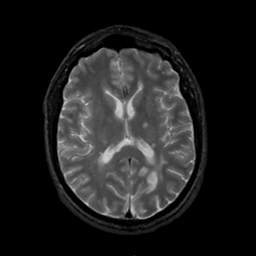

MR Study #1, February 10, 1991 -- Slice #28